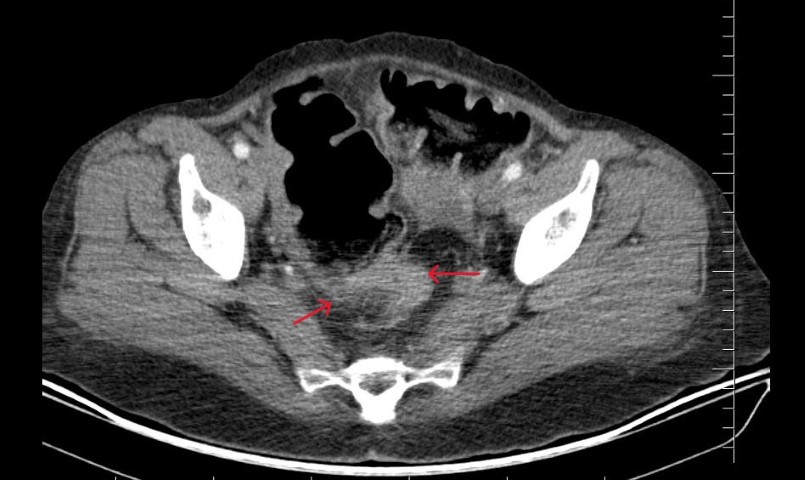

Viranşehir Devlet Hastanesi'ne uzun süredir devam eden karın ağrısı ve kabızlık şikâyeti ile başvuran 40 yaşındaki kadın hastamızda yapılan kapsamlı tetkikler sonucunda rektum kanseri teşhisi konulmuştur.